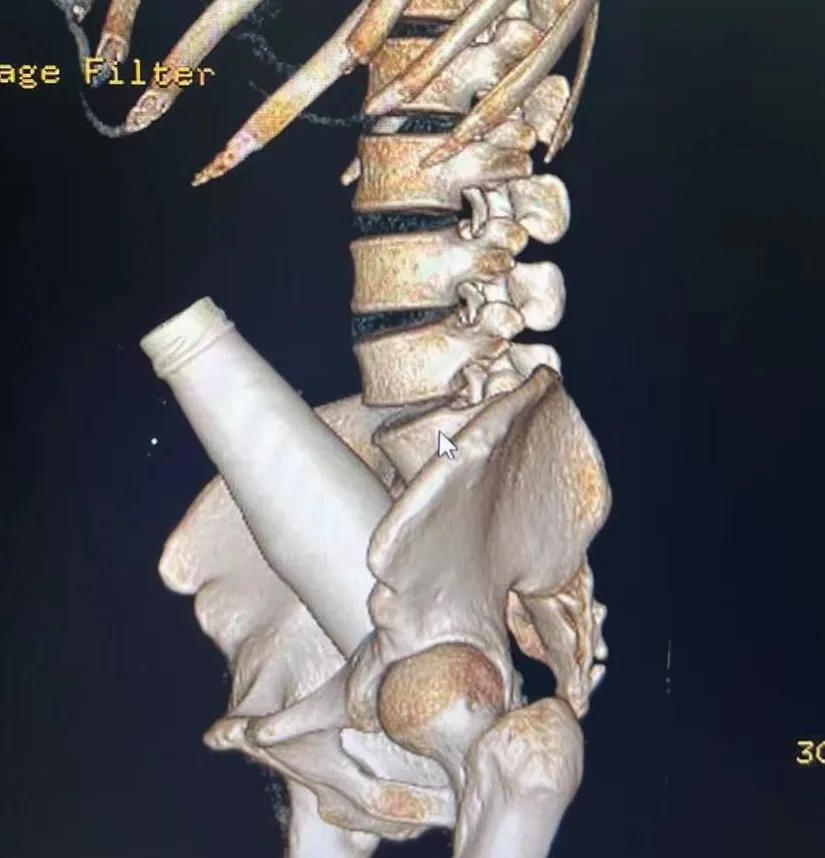

正如上所说,肛肠科之所以能够在每家医院成为传奇那是有它独特之处的,因为医院大部分劲爆的新闻都出自肛肠科。上次我们所讲的“菊花掏玻璃瓶”只是管中窥豹而已,各种稀奇古怪的作品都能进去菊花,吃的、用的、看的,能动的、不能动的,没有最劲爆只有更劲爆!

注定成名的瓶子